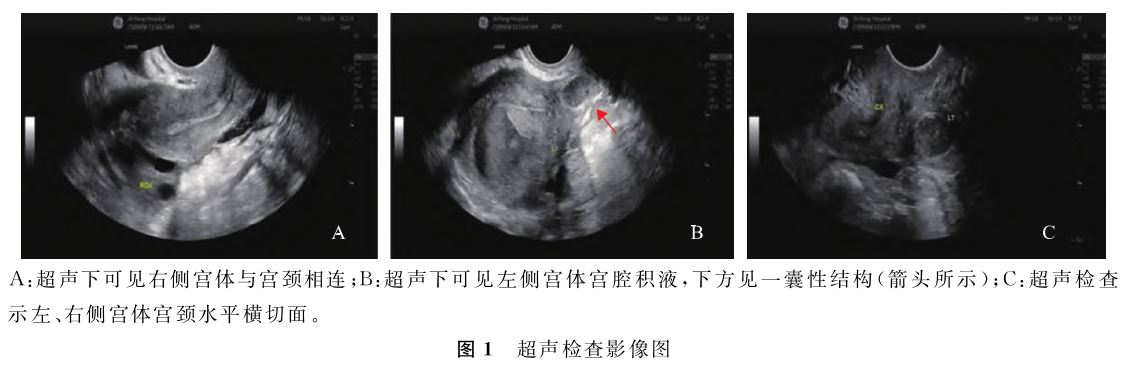

检查示:盆腔偏右侧探及一正常大小子宫,下方与宫颈相连,子宫内膜厚约5mm;盆腔偏左侧探及一肌性结构,大小约62mm×52mm,其内可见无回声区,透声差,有流动感;肌性结构下方探及一直径约19mm囊性结构,壁厚,内透声差;左侧肌性结构与右侧子宫未见明显相通。右侧卵巢大小正常;左侧卵巢稍增大,内探及一36mm×30mm囊性结构,透声差。超声提示:子宫畸形:右侧单角子宫并左侧残角子宫可能性大(左侧宫腔积液),双子宫不除外(图1);左侧卵巢内巧克力囊肿

可能。泌尿系超声提示:左肾未探及,右肾代偿性增大。下腹部+盆腔MRI示:(1)右侧单角子宫伴宫颈水平相连伴有功能性子宫内膜的左侧残角子宫;左侧宫腔下方囊状影,考虑为左侧阴道阻塞积血可能性大;(2)右肾孤立肾(图2)。